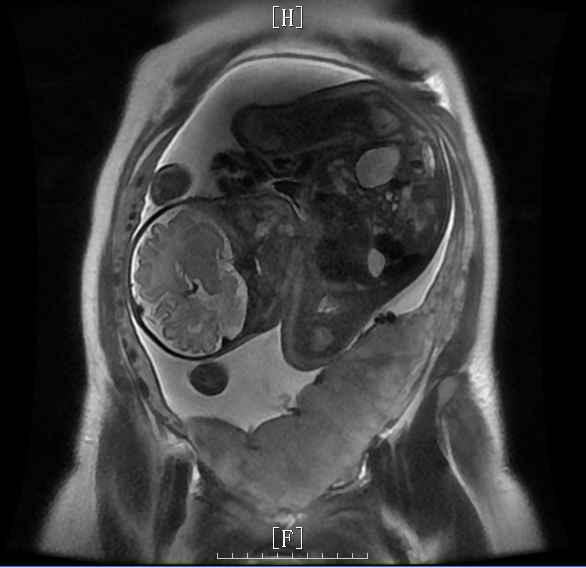

2023-10-23,我院胎盘MRI:晚孕;中央型前置胎盘,左侧壁局部胎盘植入可能(宫腔内见胎儿影,横位,胎盘位于子宫前壁、左壁、后壁,矢状位示宫颈内口后缘被完全覆盖,冠状位及横断位示胎盘左侧壁见局限性凸起,局部子宫肌层菲薄。宫颈未见明显异常信号。盆腔内未见软组织肿块或积液影。